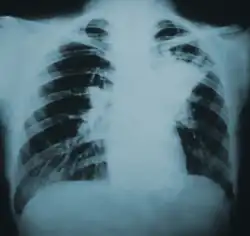

![]() | |

| Lung infiltration in blastomycosis. | |

Blastomycosis manifests as a primary lung infection in about 79% of cases.[8] The onset is relatively slow, and symptoms are suggestive of bacterial pneumonia, often leading to initial treatment with antibacterials. Because the symptoms are variable and nonspecific, blastomycosis is often not even considered in differential diagnosis until antibacterial treatment has failed, unless there are known risk factors or skin lesions.[8] The disease may be misdiagnosed as a carcinoma, leading in some cases to surgical removal of the affected tissue.[19] Upper lung lobes are involved somewhat more frequently than lower lobes.[20] If untreated, many cases progress over months to years to become disseminated blastomycosis.

Blastomycosis in the lungs may present a variety of symptoms, or no symptoms at all.[8] If symptoms are present they may range from mild pneumonia resembling a pneumococcal infection to acute respiratory distress syndrome (ARDS).[8] Common symptoms include fever, chills, headache, coughing, difficulty breathing, chest pain, and malaise.[8] Without treatment, cases may progress to chronic pneumonia or ARDS.[8]